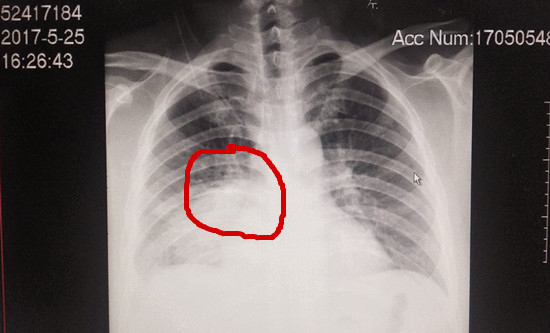

接诊的该院肺病一区副主任医师彭景钦检查后发现,谢先生右肺存在大片炎症,建议即刻办理住院手续作进一步的检查诊治。

(门诊胸片显示右下肺大片密影)